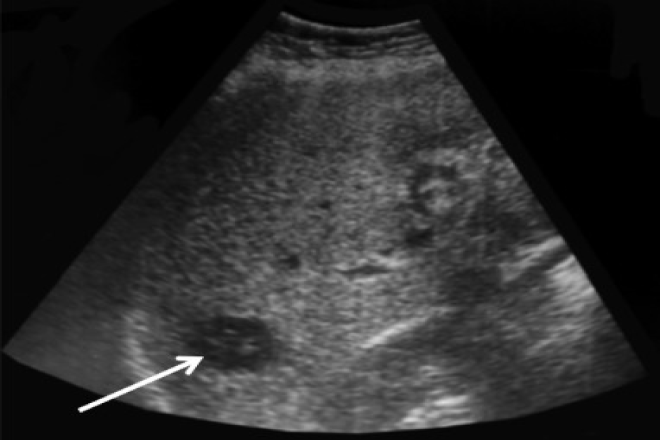

El ultrasonido abdominal es operador dependiente, reportándose en estudios recientes una sensibilidad mayor al 60% y una especificidad mayor al 90% su sensibilidad  para la detección de nódulos en hígado  cirrótico es particularmente baja.las guías actuales recomiendan el uso de ultrasonido abdominal cada 6-12 meses  como método de escrutinio  y vigilancia en pacientes  con alto riesgo el uso adicional de AFP es controversial. los métodos de imagen más confiables para los propósitos  de diagnostico y estadiaje  del tumor  son la TC en tres faces  y la resonancia magnética dinámica  contrastada  en tres fases el CHC debe su irrigación  sanguínea  predominantemente a la arteria hepática  mientras que el resto se encuentra irrigado  por el sistema  arterial y venoso  portal.

Se  puede realizar de manera  confiable si presenta alguna de las  siguientes características. Tumoración hepática  focal mayor de 2 cm  identificada  mediante una imagen  que muestra el realce característico  con el contraste  en la fase arterial  y lavado rápida  en la fase venosa ,tumoración hepática focal con comportamiento atípico por imagen o tumoración hepática  documentada en el hígado  no cirrótico con biopsia  compatible.